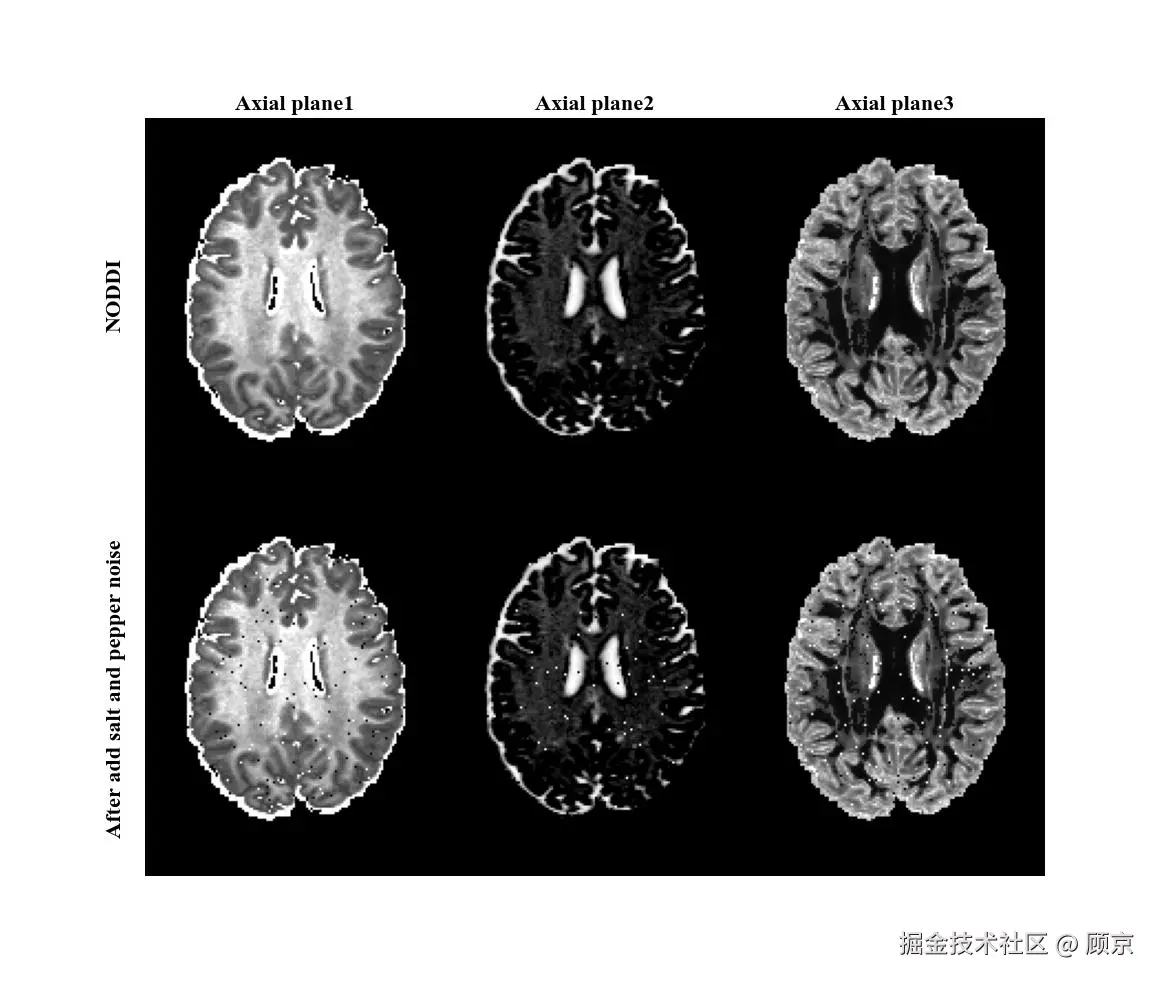

除了添加高斯噪声,还可以添加椒盐噪声,这是一种数字图像中常见的噪声类型,具体表现为在图像上随机出现黑色和白色的像素点,如图2所示。椒盐噪声之所以得名,是因为其表现形式与“椒”和“盐”的颜色相似。在这里,“椒”代表黑色(pepper),而“盐”代表白色(salt)。当这种噪声出现在图像上时,就像是图像上撒了黑胡椒和白盐粒一样,因此得名椒盐噪声。

add salt and pepper noise.jpeg

图2 添加椒盐噪声